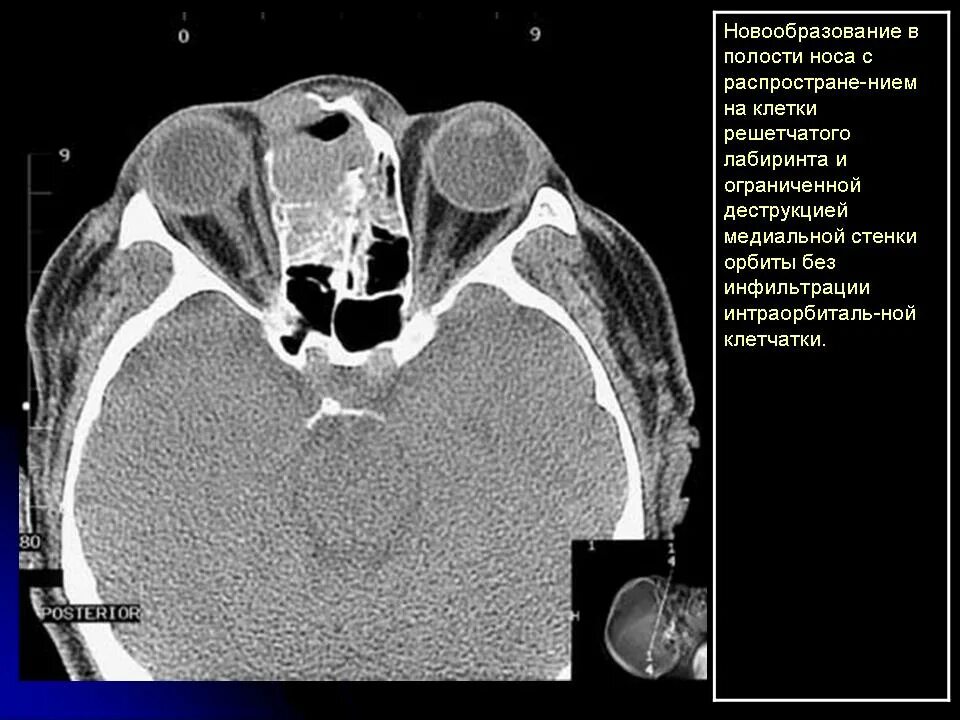

Данные кт